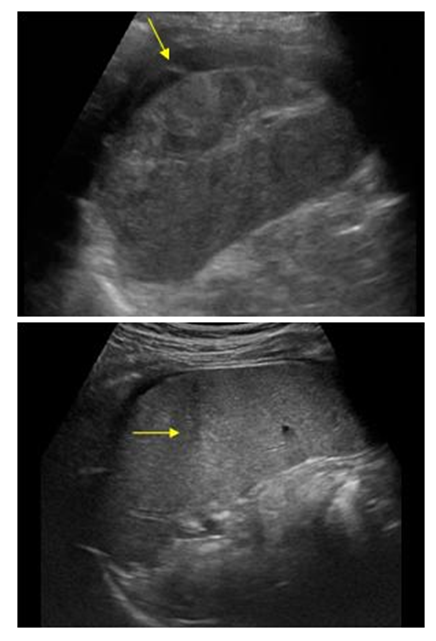

![]() | Figure 1. Ultrasound of the abdominal cavity of patient K. with catatrauma. Free fluid around the liver |

![]() | Figure 2. Ultrasound of the abdominal cavity of patient B. with catatrauma. Free fluid around the spleen |